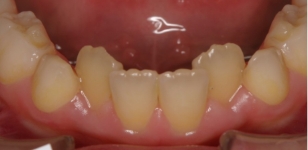

永久歯を抜かずに矯正できたが、自然な歯並びの変化(犬歯部で狭くなる)のために、下顎前歯にガタツキが発生した。